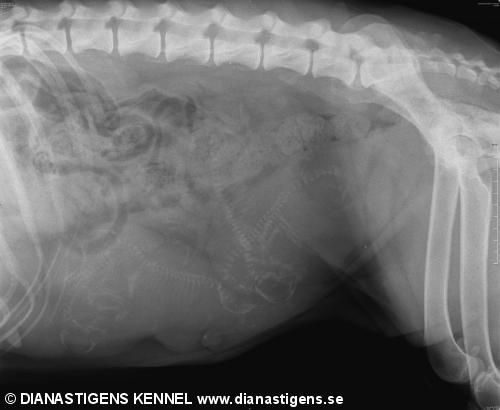

Grattis i efterskott till NC-barnen! Här i Björkland väntar vi smått igen. Var i Arvidsjaur och röntgade Diva. Så runt den 23 februari borde dom komma. Spännande :) Ska fixa fler bilder och göra ett ryck med hemsidan nu. Så även när valparna har kommit. Promise! Kram på er

Vad kul, hoppas på några fler än vad som syns.